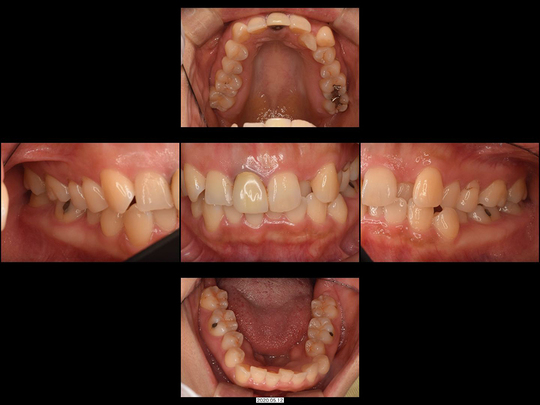

Oさん 40代 女性

矯正前

画像をクリックで拡大

矯正後

治療の説明

上の前歯が磨きづらく、紹介された矯正専門医院に相談したところ、「上の前歯2番目を抜歯して3番目の歯を2番目の形にする」と言われたケースです。

精査の結果、すでに3番目の歯の歯ぐきが下がってきていることから、これを2番目の歯として使った場合、見た目が非常に不自然になる可能性および不必要に削るリスクが高すぎると判断できました。また、唇の形とそのスマイルラインを考慮した結果、通常通りの小臼歯抜歯併用の全体矯正で対応しました。

治療の期間・回数

18か月、20回

​費用

858,000円